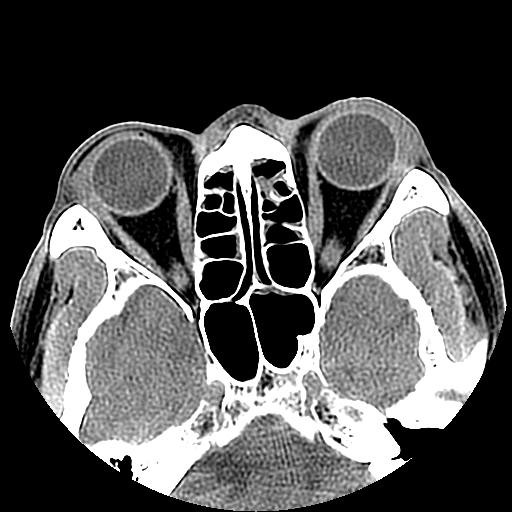

以下是引用liaoqiang在2008-7-16 21:15:00的发言:[br]右侧鼻骨骨折

以下是引用zxd95在2008-7-16 21:39:00的发言:[br]右侧上颌骨额突骨折。[br][br][br][br]